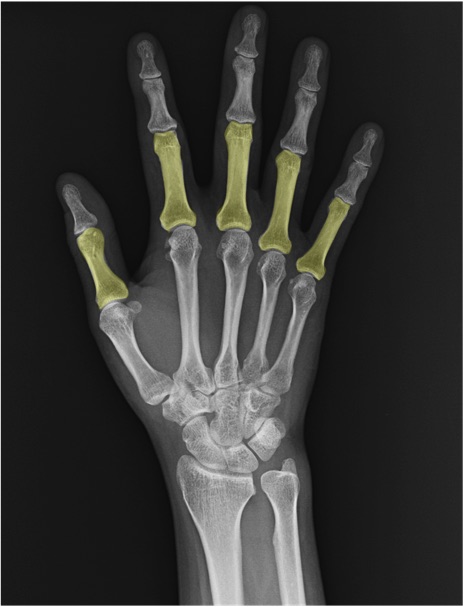

基節骨(proximal phalanx)の手関節レントゲン画像における正常解剖

中手骨(metacarpal bone)

中節骨(middle phalanx)

末節骨(distal phalanx)

MP関節(metacarpophalangeal joint)

PIP関節(proximal interphalangeal joint)

DIP関節(distal interphalangeal joint)